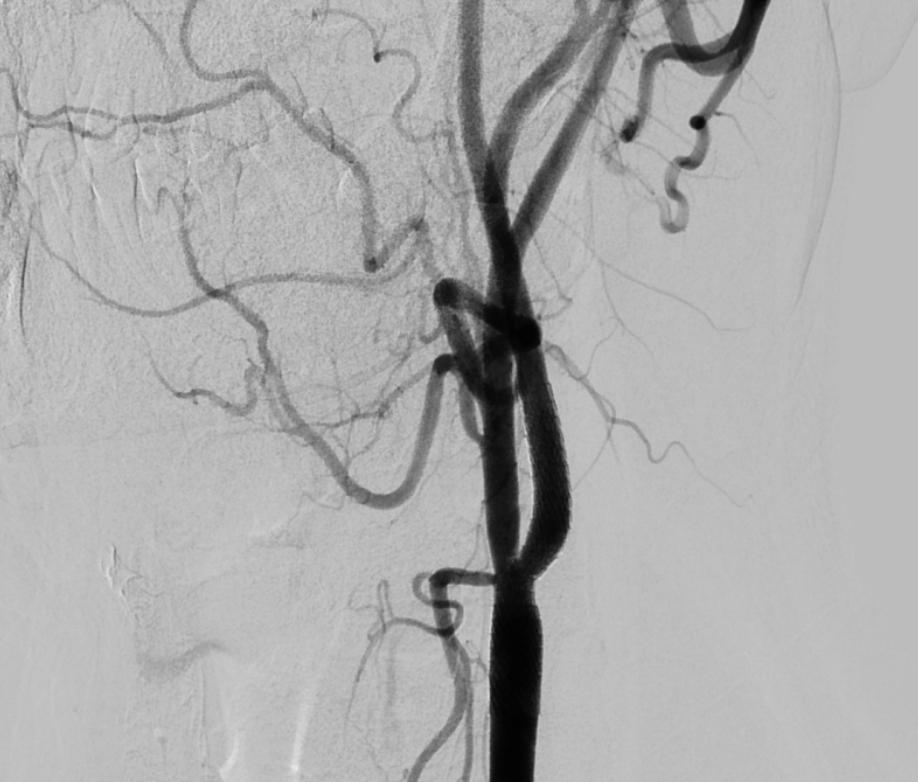

该例患者手术最大难度在于变异主动脉弓情况下左侧颈总动脉开口导丝到位困难,手术通路难以建立。张桂莲教授团队小心操作、大胆探索,最终开创性使用SIM1导管及硬泥鳅导丝导引及长轴交换的办法成功建立导管通路,最终成功置入颈动脉支架(图2),患者术后恢复良好。该例高难度颈内动脉支架植入术的成功实施充分体现了我院神经内科神经介入水准。

图2左侧颈内动脉支架置入术后,残余狭窄约20%